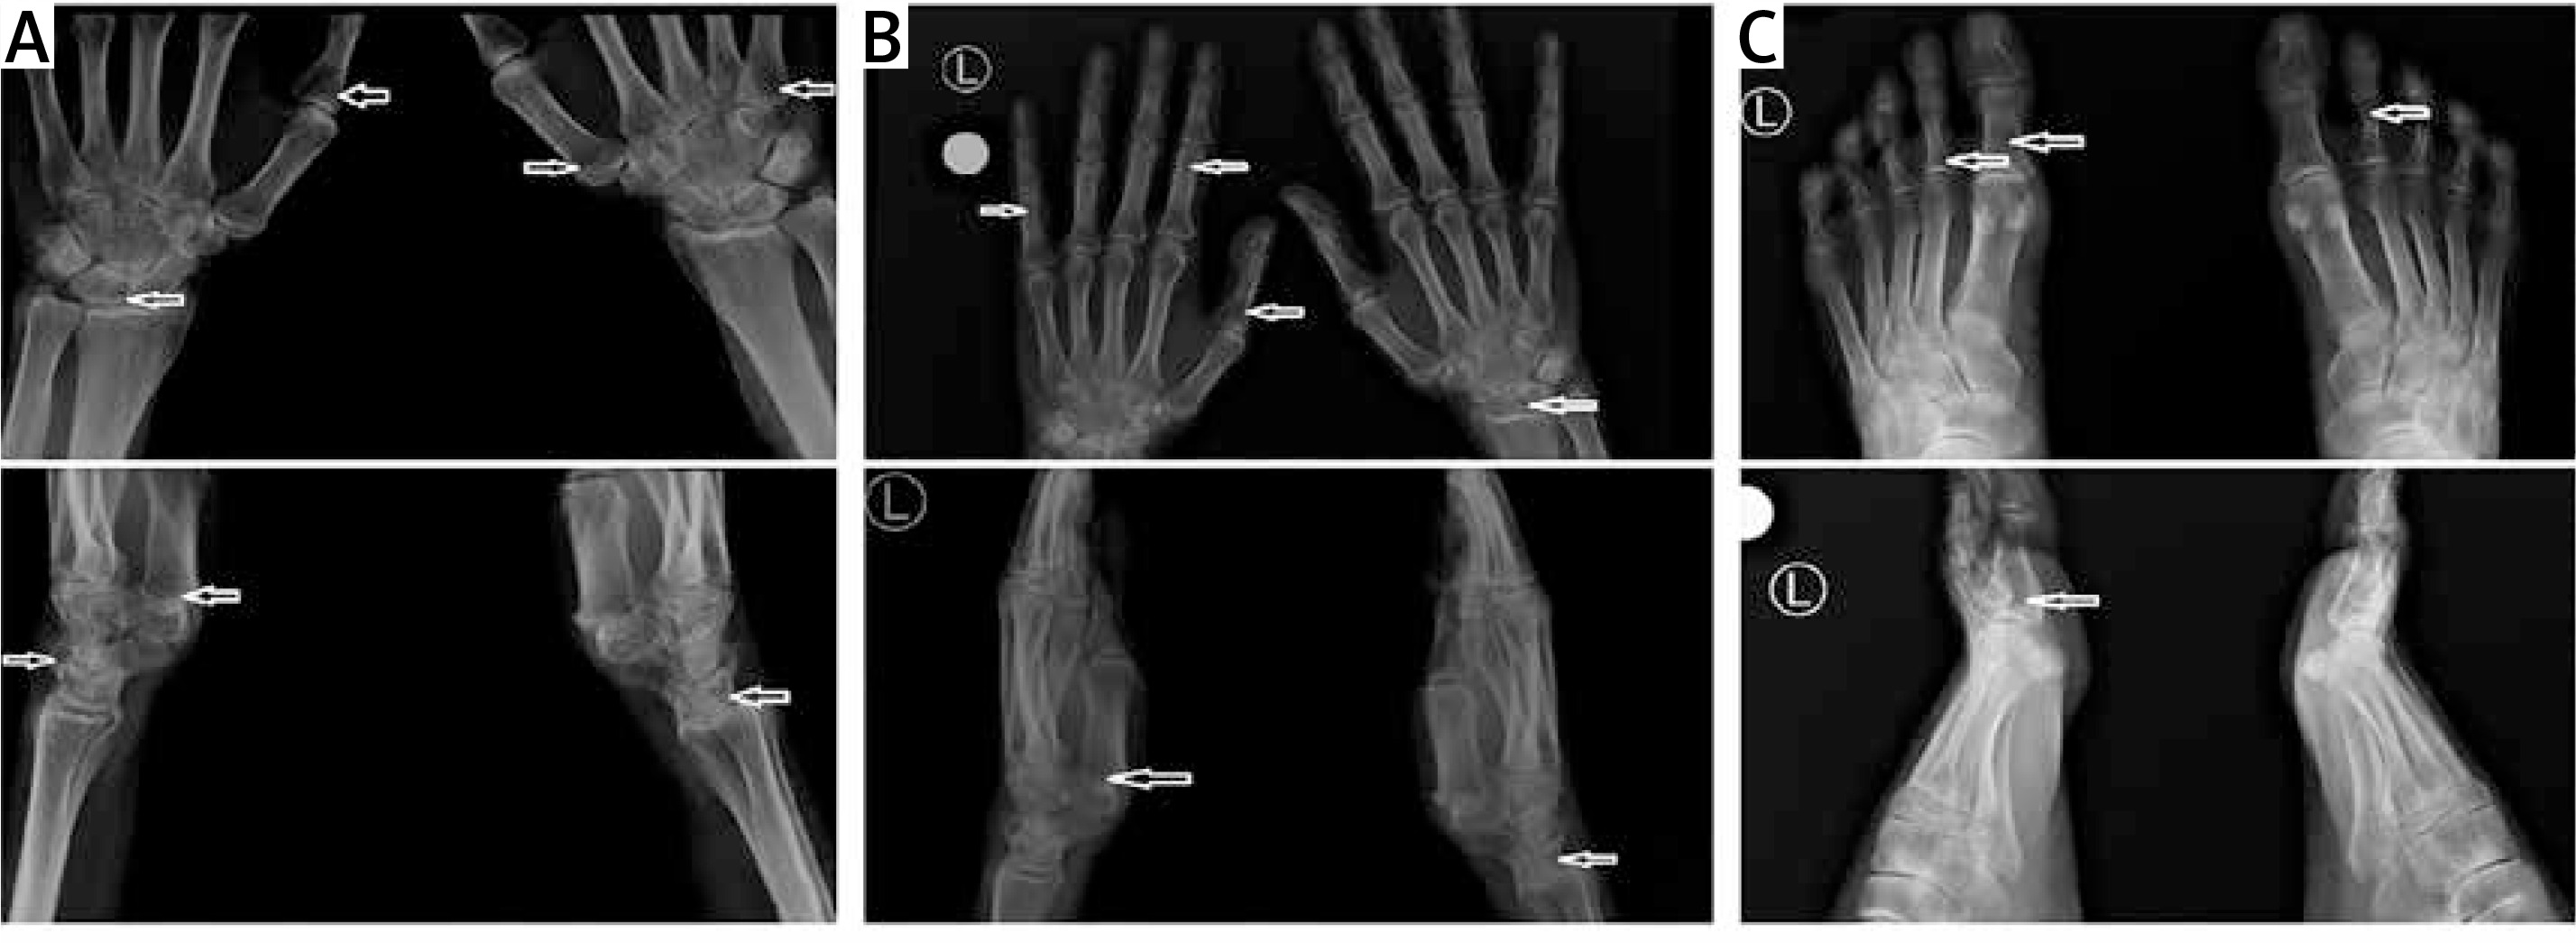

Taking into consideration the suspicion of Nasu-Hakola disease, hand and foot radiography (RG) was performed. The examination showed a single cyst within the right scaphoid and lunate bone, and minor cysts in the capitate and the hamate bones bilaterally (Figure 2 A). Additionally, the imaging revealed mild cyst lesions in the phalanges of both the right and the left hand (right: proximal phalanges of the second, third, and fourth finger; left: proximal phalanges of the third and fifth finger) (Figure 2 B). Moreover, in foot radiography, single cysts were found in the proximal phalanx of the first toe and the first metatarsal (both bilaterally) (Figure 2 C). This radiological image is highly characteristic of Nasu-Hakola disease; no other cause of dementia is known to be accompanied by polycystic bone lesions.

Figure 2

Bone cysts visible on the X-ray (arrows). The upper images are anteroposterior projections, and the lower images are lateral projections. A – Radiographs of the right and left wrist. B – Radiographs of the right and left hand. C – Radiographs of the right and left foot